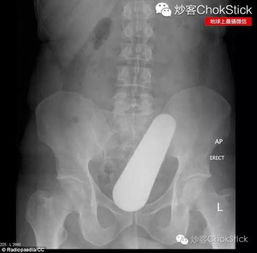

据Dailymail报道,近日,法国图卢兹的一家医院遭遇了一场惊险又荒诞的事件。一名24岁的男子因直肠内塞入一枚长达8英寸(约20厘米)的一战时期炮弹,紧急前往朗格伊(Rangueil)医院急诊科求医。由于炮弹存在爆炸风险,医院被迫紧急疏散了部分员工和患者。

事发于上周六深夜,该男子因极度不适被送往急诊。据调查消息人士称,男子承认自己将一个大物体塞入了直肠,但起初并未说明具体为何物。直到医生在手术过程中将其取出时,才惊觉这竟然是一枚一战时期的德军37毫米口径炮弹。 由于无法确定这枚生产于1918年的炮弹是否仍具有爆炸性,医院立即启动了应急预案。消防队在现场待命,防爆专家被紧急召集到手术室进行评估,同时急诊科周边设立了安全警戒线,部分病区进行了疏散。

幸运的是,经过专家检查,这枚由黄铜和铜制成的炮弹已失去活性,不会发生爆炸。